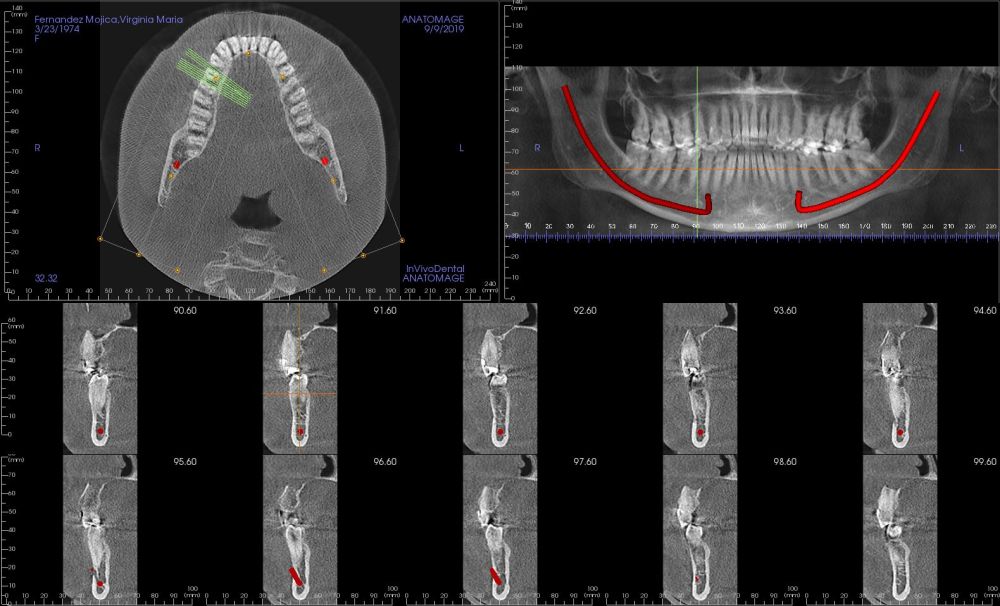

Presentamos el caso de una paciente de 47 años que acude al servicio de cirugía maxilofacial por dolor en el área sinusal derecha en Junio de 2020. Se realizó una radiografía panorámica en la que se observó una imagen sospechosa en la zona del primer cuadrante. Dichos hallazgos se confirmaron con la realización de una tomografía axial computarizada (TAC) facial y una resonancia magnética en las que se identifica una extensa lesión tumoral que ocupaba el seno maxilar derecho e infiltraba el suelo de la órbita derecha y fosa nasal derecha (Figuras 1, 2 y 3). Tras la realización de una biopsia, se confirmó la presencia de un carcinoma adenoide quístico. De este modo, se planificó la extirpación quirúrgica y la fijación mediante placas preformadas sobre un modelo impreso en poliamida (Figura 4).

Bajo anestesia general, se realizó la resección quirúrgica junto con la fijación de dos placas preformadas y colocación simultánea de dos implantes cigomáticos y un implante endoóseo en posición del 2.1 (Figuras 5 y 6). Debido a la presencia de márgenes quirúrgicos comprometidos en el informe anatomopatológico, se indicó la administración de radioterapia adyuvante. Por este motivo, se decidió realizar un puente provisional dentosoportado de 1.7 a 2.3 (Figura 7) para mejorar la situación estética y funcional de la paciente durante todo el proceso y evitar un colapso de los tejidos blandos por la radioterapia. Para ello, se tallaron los molares (1.7, 1.6) e incisivo lateral y canino (2.2, 2.3), y se fabricó un puente fresado en polimetilmetacrilato (PMMA) con refuerzo metálico (Figuras 8 y 9).